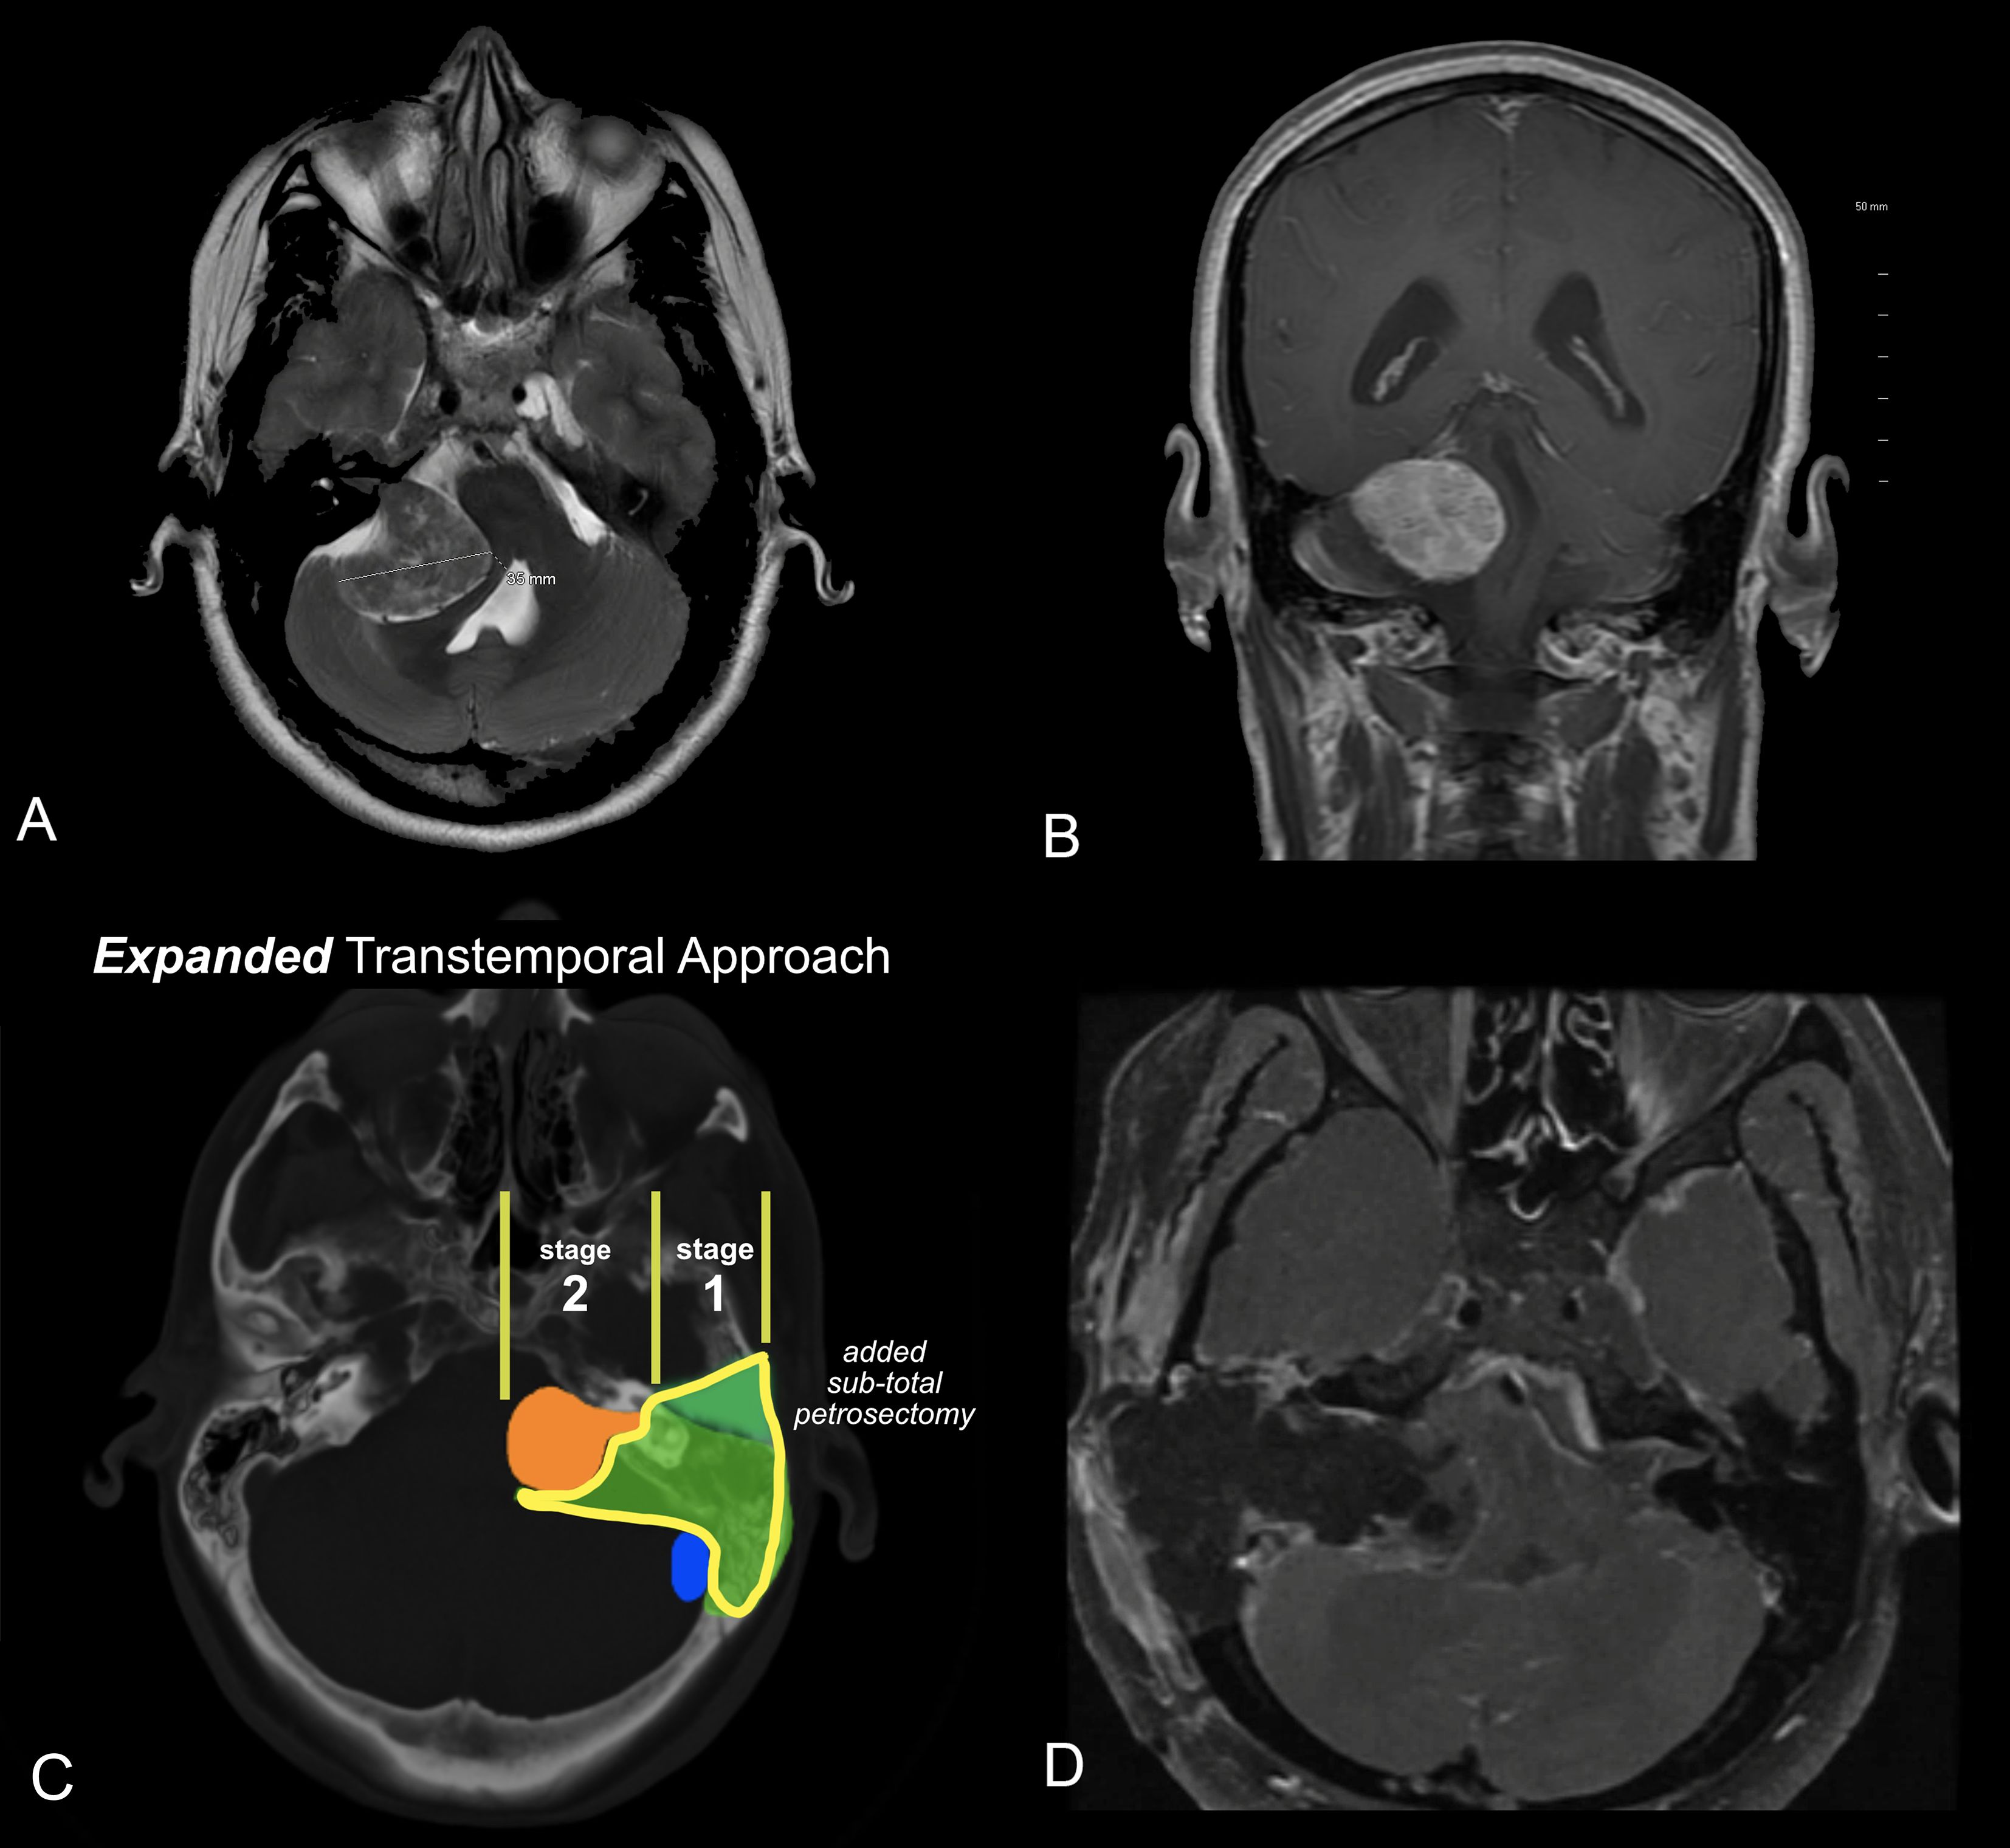

Introduction: Acoustic neuroma (AN) is a benign tumor of the vestibulocochlear nerve, with increasing detection due to improved imaging. Treatment decisions are complex, requiring an individualized approach based on tumor size, location, growth rate, and patient-specific factors such as hearing and vestibular function. Results: Treatment options include observation, microsurgery, and stereotactic radiosurgery. Hearing preservation is prioritized in select cases using middle cranial fossa or retrosigmoid approaches, while translabyrinthine surgery is preferred for larger tumors or disabling dizziness. Stereotactic radiosurgery offers a non-invasive alternative but has variable long-term hearing outcomes and potential tumor regrowth. Vestibular rehabilitation is essential post-treatment, particularly after surgical resection. Discussion: Decision-making depends on patient age, tumor progression, and symptom severity. Younger patients with small tumors may benefit from early intervention to preserve hearing, while older patients with severe imbalance achieve better quality-of-life outcomes with surgery. Stereotactic radiosurgery remains an option for patients unable to undergo surgery, though its long-term efficacy and side effects require careful consideration. A multidisciplinary approach is essential to optimize treatment outcomes. Summary: AN management must be tailored to individual patient profiles. This review integrates current literature and expert clinical experience to guide otolaryngologists, neurologists, and oncologists in treatment planning. Future research should refine treatment algorithms and improve functional outcomes.